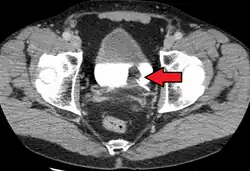

Tomografia komputerowa raka pęcherza moczowego. Guz oznaczony niebieską strzałką, czerwoną strzałką oznaczono zakrzepicę lewej żyły biodrowej zewnętrznej

Rak pęcherza moczowego oznaczony strzałką

Postawione podczas cystoskopii podejrzenie raka inwazyjnego lub potwierdzenie histopatologiczne obecności raka inwazyjnego wskazują na konieczność wykonania tomografii komputerowej (TK) lub rezonansu magnetycznego (MRI) miednicy i brzucha w celu oceny zaawansowania choroby[151][152]. Celem wykluczenia rozsiewu do płuc wykonuje się zdjęcie rentgenowskie klatki piersiowej (RTG) lub tomografię komputerową klatki piersiowej[135].

Tomografia komputerowa

Tomografia komputerowa (TK) jest podstawowym badaniem obrazowym służącym do oceny zaawansowania raka pęcherza moczowego[153][154]. Tomografia komputerowa pozwala na dobrą dokładność diagnostyczną oceny obecności rozsiewu do narządów odległych i lokalnych węzłów chłonnych[153]. Czułość badania w zakresie rozpoznawania raka pęcherza moczowego jest oceniana na 85%, a swoistość 94%[155][154].

Nowotwór w zakresie pęcherza moczowego może być widoczny jako pogrubienie ściany narządu, które może ulegać wzmocnieniu kontrastowemu[156][157]. Badanie pomaga rozpoznać naciekanie tkanek okołopęcherzowych (T3), jednak nie umożliwia wiarygodnego rozróżnienia guzów nieinwazyjnych (Ta) od naciekających błonę mięśniową (T1)[158]. Ocena inwazji sąsiednich narządów (cecha T4) za pomocą TK może być trudna, szczególnie w przypadku podejrzenia nacieku pochwy i macicy, gdy oddzielająca je tkanka tłuszczowa jest cienka[156].